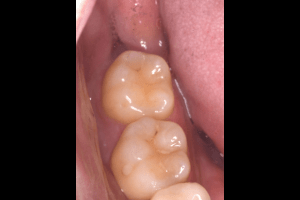

右上下の親知らず抜歯症例

- 右上抜歯前の写真

- 右上抜歯後の写真

- 右下抜歯前の写真

- 右下抜歯後の写真

| 抜歯内容 | 右上8番普通抜歯 右下8番の半埋伏抜歯 |

| 治療方針 | 右上8番と上顎洞との位置関係と、右下8番と神経の位置関係を確認するためにCT撮影を行いました。 右下8番は半埋伏なので歯ぐきを切開後、骨を切削したり、歯を分割して抜歯しています。 切開した歯ぐきの箇所は2箇所縫合し、後日抜糸しています。 右上8番は切開することなく抜歯しました。 |